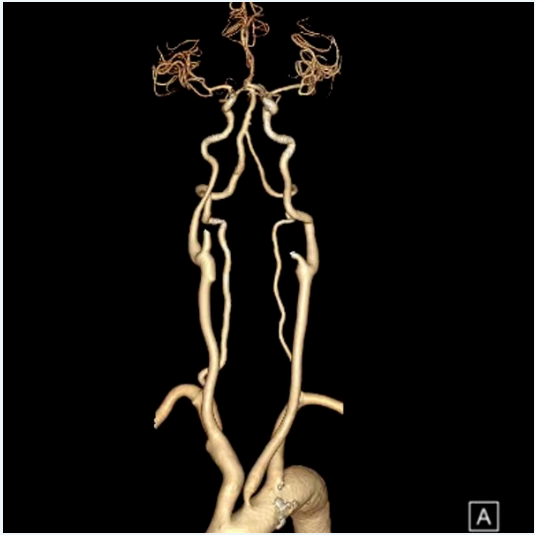

二、術前影像

image.png